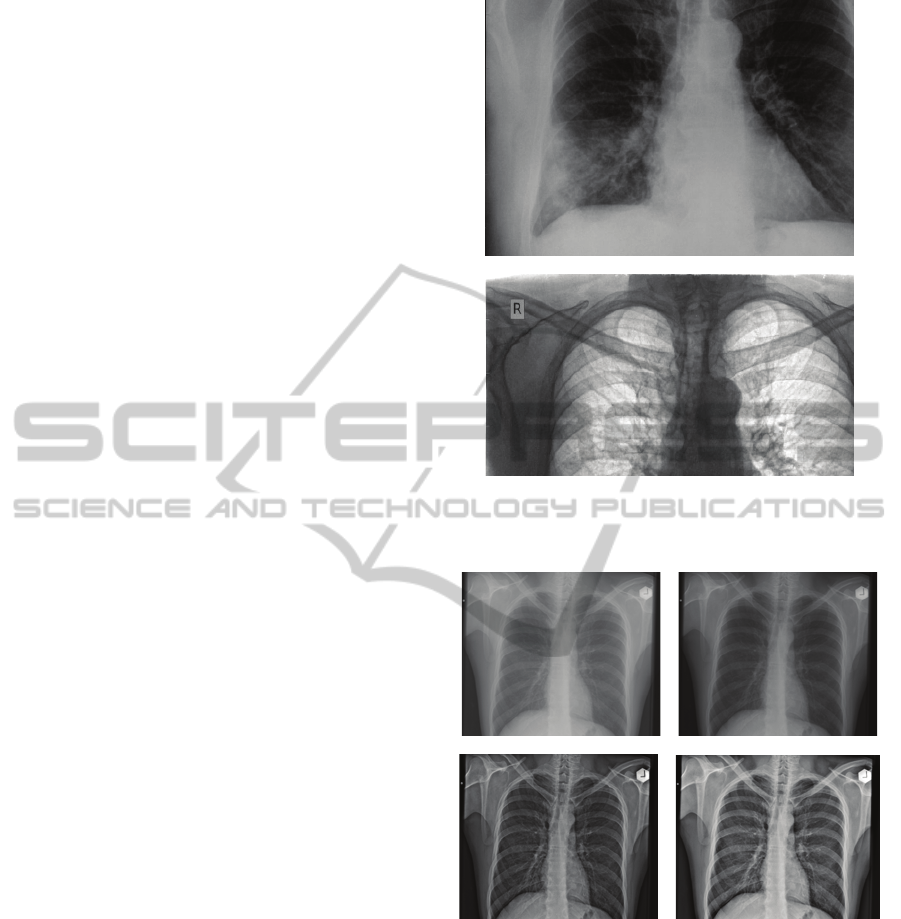

5 IMPLEMENTATION RESULTS

Two classes of digital photo cameras are used for

the development of camera-based scanning devices:

“Compact Super Zoom” (manual mode, 12x optical

zoom, 12 M effective pixels, less than 1% optical

distortion, <300 g) and „Compact” (manual mode,

4x optical zoom, 7 M effective pixels, ~ 1% optical

distortion, ~ 220 g). Cameras of the “Compact Super

Zoom” class have provided much greater

opportunities for developing devices which will

substantially expand the potential applications of the

system. All results described below are based on the

use of devices with this type of camera.